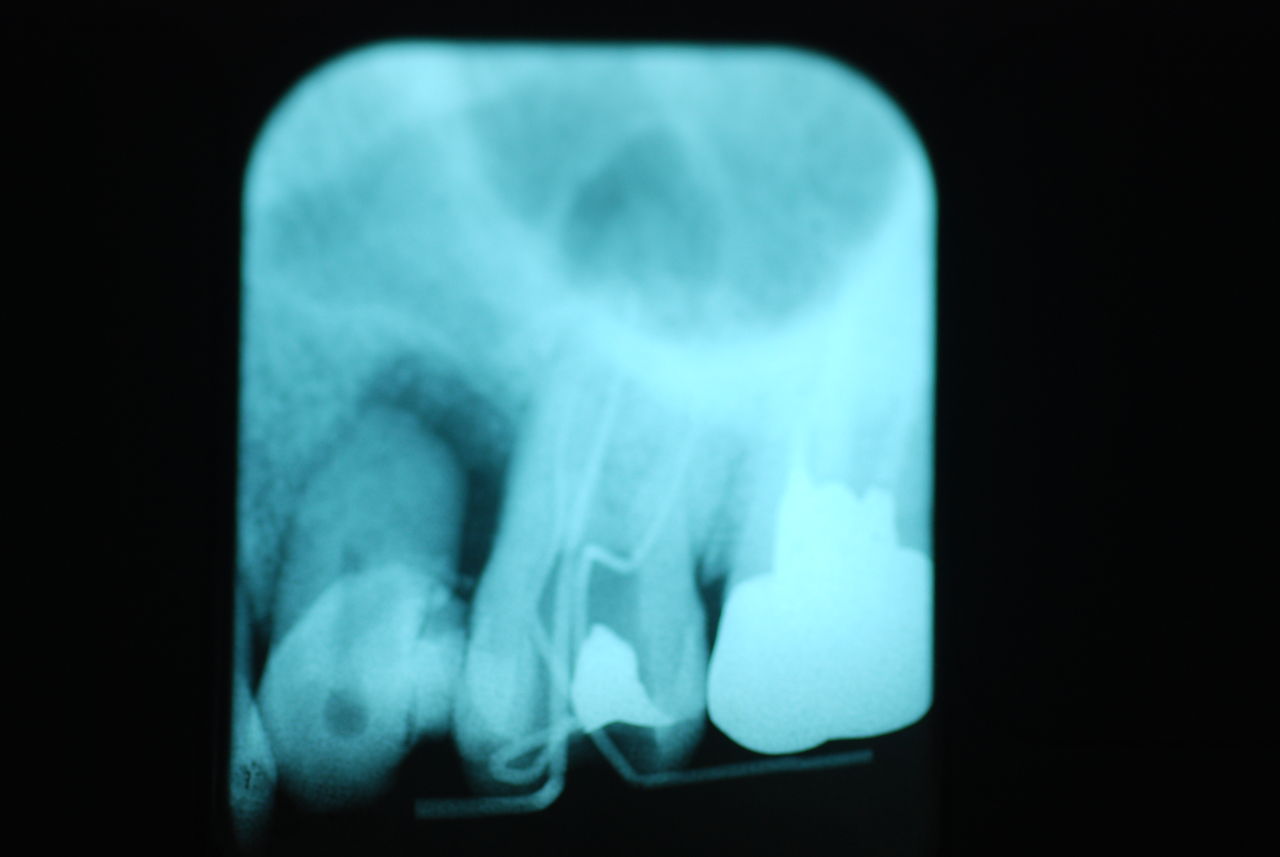

相談しても“問題無い”の説明だけだそうです。調べたところ歯周病は進行しているし、奥歯の大きい歯2本ずつ計4本はしっかり噛んでいないのです。よく噛めないというのはそのことのようでした。これを矯正的に元に戻すことはできない訳ではありませんが、時間と手間がかかるのは間違いないことです。

歯を削らないといいましても結局歯の間を削りスペースを確保したそうですから、何らかの歯に対する傷害はしているのです。それは虫歯や歯周病を起こしやすい理由にもなりますからこれからも要注意なのです。二年間という貴重な時間を費やしていますから患者本人は大変だったと思います。そして二年間を要したならば更に二年間動かないようにするための入れ歯やマウスピースを装着し続けなければいけないのです。